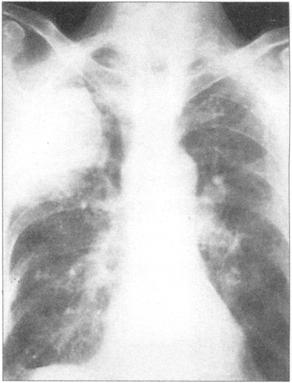

①周围性发绀及周围静脉扩张是由COPD引起的CO2潴留的主要特征(图76)。②脊柱侧后凸常预示患者有某种呼吸系统疾病的倾向(图77)。③结核的X线表现(图78)。④肺尖部结核所致的纤维化多引起上胸部变平(图79),由于脊柱常受累,故多有成角。⑤支气管肺癌(图80)。⑥大叶肺炎患者常伴发单纯疱疹病毒感染(图81、图82)。⑦如肺组织萎陷(如气胸),则胸片上无法看到肺纹理(图83)。

图78 结核,在肺上叶可见空洞

图79 肺尖结核。由于先前的结核靠造成拉平的顶端,伴有由脊柱弯曲引起的成角